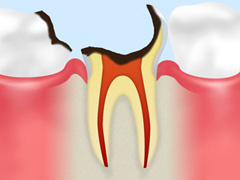

C2:象牙質まで進行

エナメル質の下にある象牙質まで虫歯が進行した状態。甘いものや冷たいものがしみます。

虫歯部分を削り、その穴をインレーで補完します。